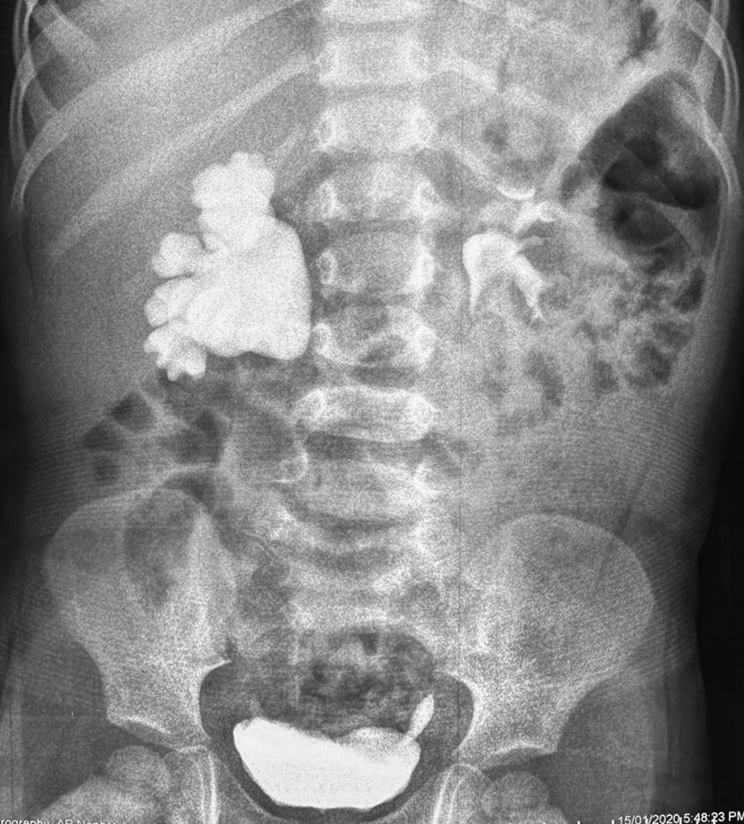

Из анамнеза известно, что пренатально была выявлена пиелоэктазия справа, в связи с чем наблюдался нерегулярно амбулаторно, периодически проводилось ультразвуковое исследование (УЗИ), со слов матери, диаметр лоханки не превышал 14 мм. В возрасте 4 лет ребенок был планово госпитализирован в урологическое отделение одной из клиник Москвы, проведено рентгеноурологическое обследование, диагностирован гидронефроз справа (рис. 1), предложено хирургическое лечение, от которого родители отказались.

Рис. 1. Экскреторная урография в возрасте 4 лет.

Fig. 1. Excretory urography at age 4.